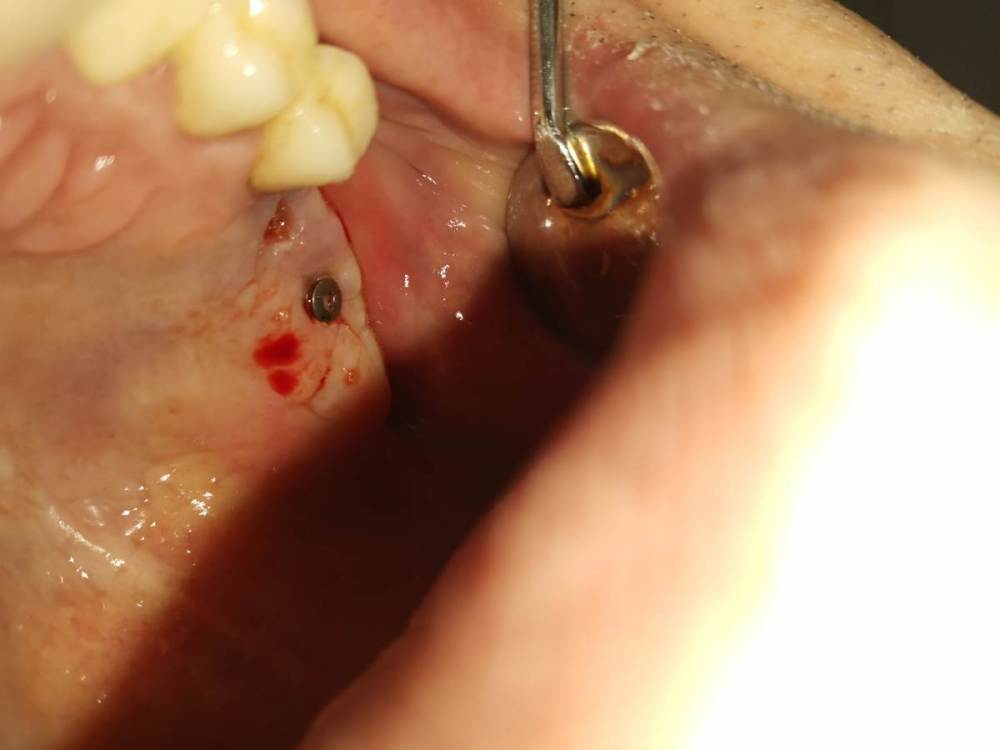

Sergiosse Опубликовано 31 августа, 2023 Поделиться Опубликовано 31 августа, 2023 Провёл ОСЛ , поставил 2 шт. ШТРАУМАН БЛ. при осмотре через неделю пост оп. было всё О'КЕЙ, на момент снятия швов обнаружил полное рассхождение лоскутов, ушил повторно. через 3 недел импланты подвижны, шейки выглядывают из десны.думаю удалить и поставить повторно через 2 месяца. У кого был такой случай ,Подскажите как решилось? Граф Лиопласт кортикальный, нужно его убирать или нет? Ссылка на комментарий

stommm Опубликовано 1 сентября, 2023 Поделиться Опубликовано 1 сентября, 2023 Импланты недозаглублены. Даже если сейчас вдруг все станет стабильно не будет десны по высоте. Лучше переделать. По поводу синуса. Посмотри что внутри после удаления имплантов. Как вариант промыть и наблюдать. Может по периметру сформироваться кость. 1 Ссылка на комментарий